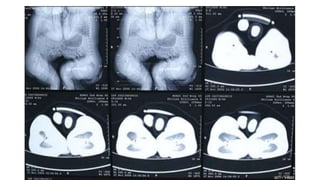

Los siameses, o gemelos unidos, han sido objeto de curiosidad y fascinación pero también de rechazo en algunas culturas. Separarlos quirúrgicamente representa un gran desafío para los médicos debido al alto riesgo que conlleva la cirugía.